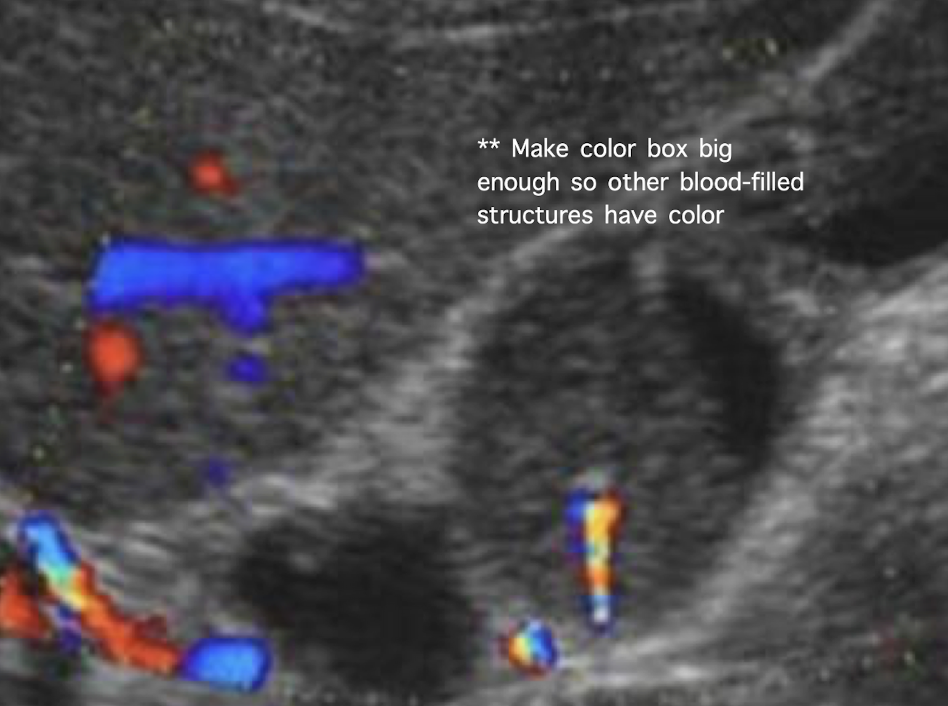

??

Type 5 choledochal cysts (Caroli’s disease)

SONO: Caroli’s disease

multiple cystic structures in the track of ducts (in the area of the ductal system) that converge at portal hepatitis

“Central dot” sign = dilated duct surrounding the adjacent HA and PV

one Mickey ear is bigger than the other